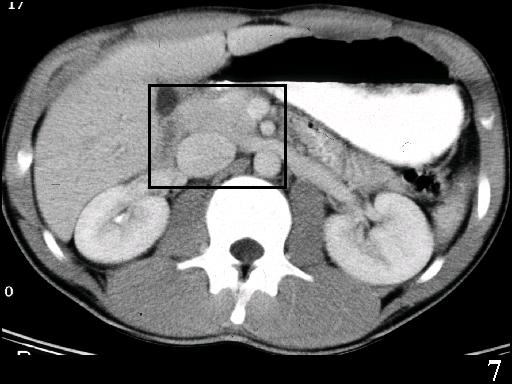

MS 190 CT 18